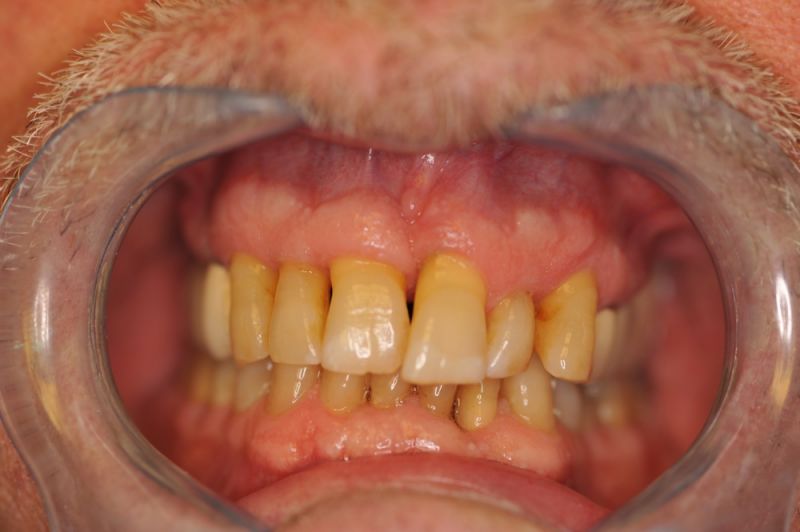

Rekonstruierter CMD Patient erscheint zum vierteljährlichen Recall

Wie üblich erscheint der Patient zum Recall.

Alles siehgt perfgekt aus. 2 mm tiefe Taschen, perfekte Mundhygiene. Die Arbeit funktioniert!